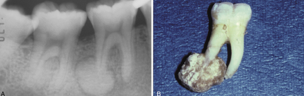

cementoblastoma

notice it is >2cm